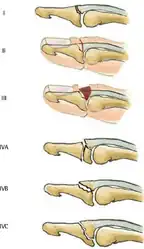

Doyle classification of mallet fingers[7]